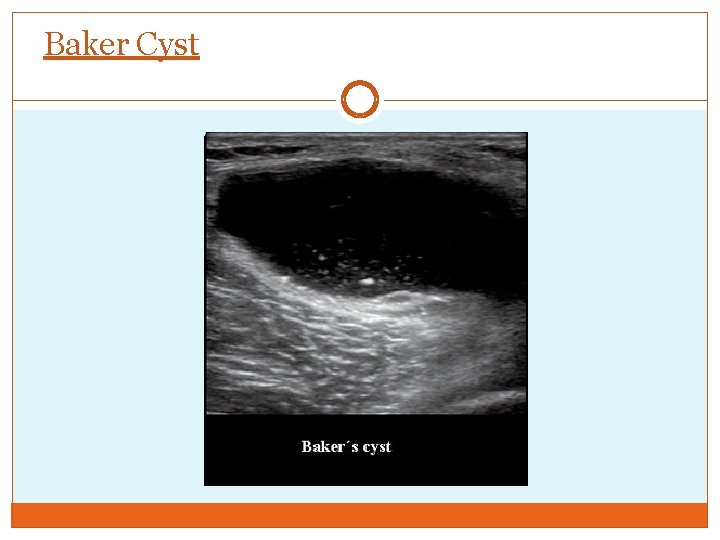

Other Ultrasound Diagnosis Lymph node Baker’s cyst Superficial thrombophlebitis Popliteal artery aneurysm

Baker Cyst